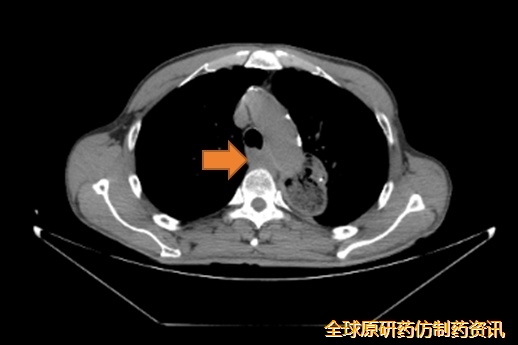

2024-07-23开始行后纵隔转移灶及左主支气管近端转移灶姑息性放疗,DT 50Gy/25F。

图3 患者接受灶姑息性放疗

图4 影像学检查结果对比

疗效评估:PR